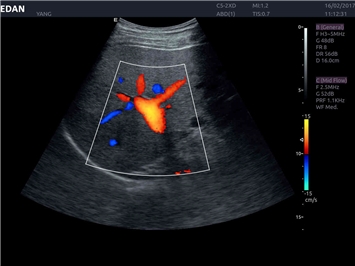

EDAN Acclarix LX4 представляет собой инновационную ультразвуковую систему, построенную на усовершенствованной платформе Acclarix. Сочетание высокого качества визуализации с интеллектуальным рабочим процессом делает эту систему оптимальным выбором для клиник, ценящих эффективность и экономичность.

• Сосудистой диагностики

Энергетический допплер:

Да

Цветовой допплер: